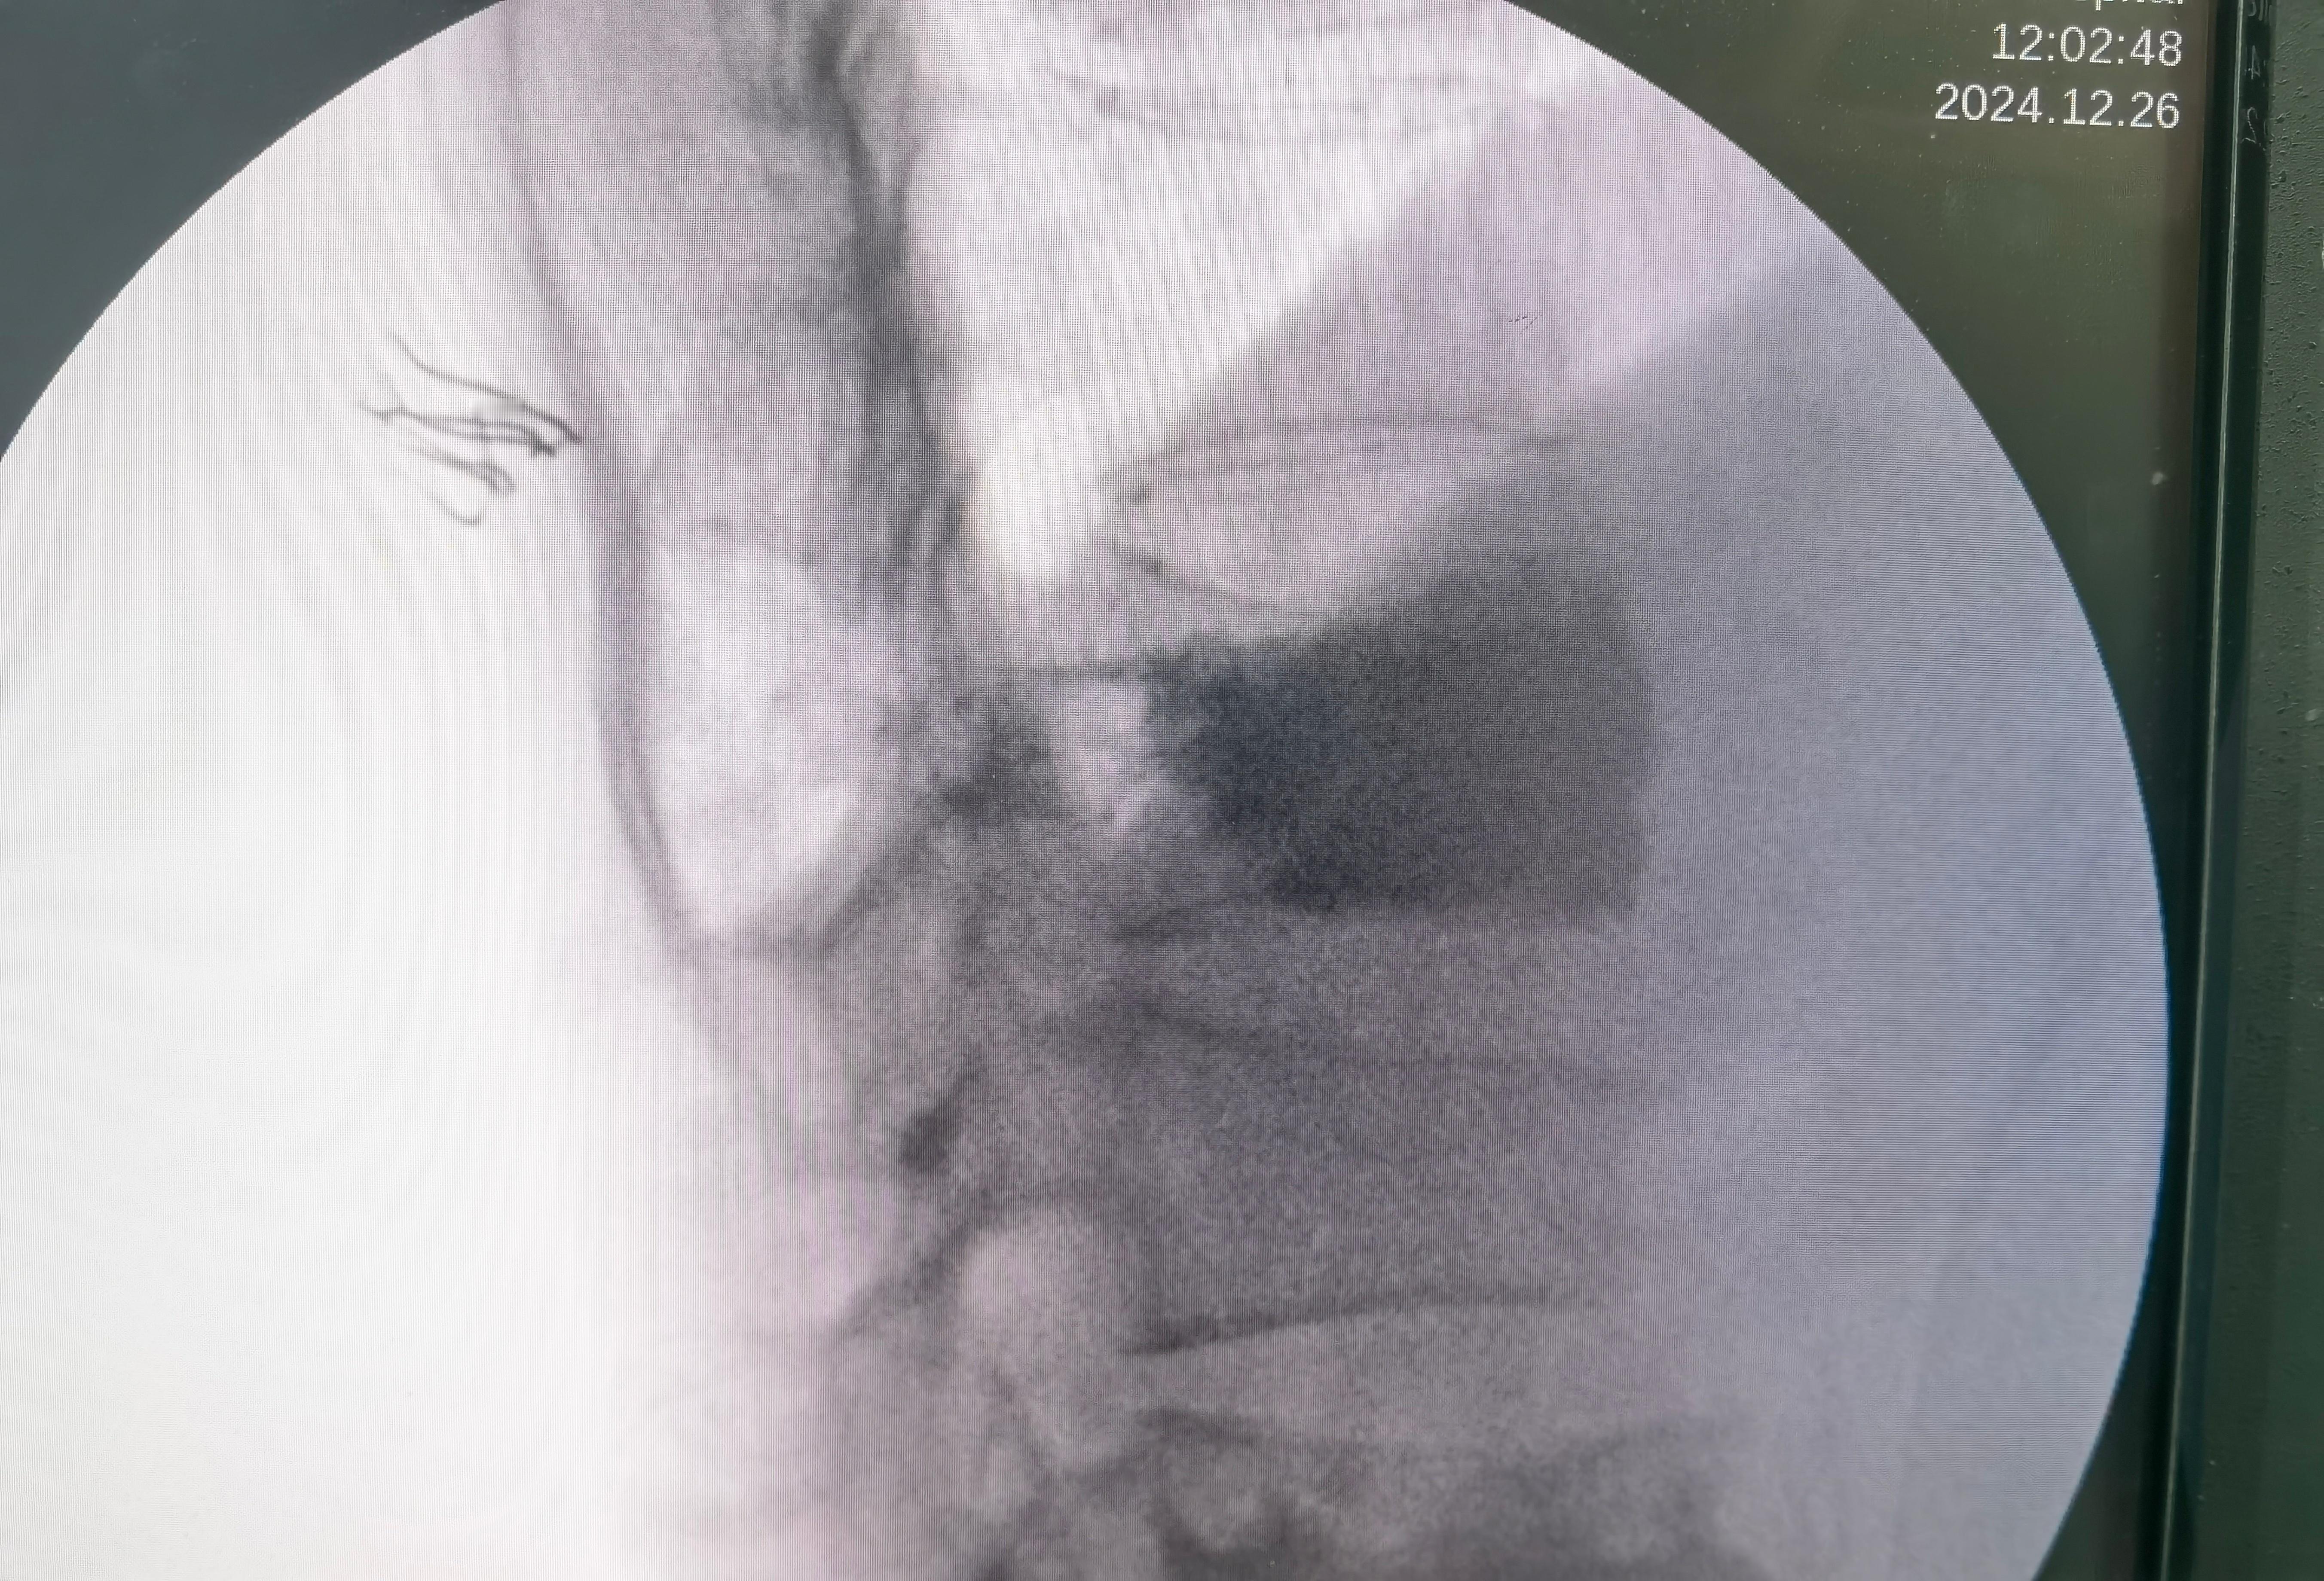

老人家的脊柱骨折首选微创手术,不建议保守治疗。看这个老太太,躺着做CT显示胸12椎体高度可,但是骨头里面有一个很大的空洞。站着拍片子这个椎体明显变矮了。这就是很恐怖的一种不稳定脊柱骨折。我们局麻注射骨水泥,注射了将近20毫升,这是极限操作,目的是把大空洞完全填满,把骨头撑起来,消灭不稳定。如果稍微少填一点,可能手术后还是不稳定,就会再骨折。这种极限操作的风险是很高的,水泥有可能漏到神经周围,导致病人瘫痪。所以大部分医生会选择做大手术,钉棒固定。